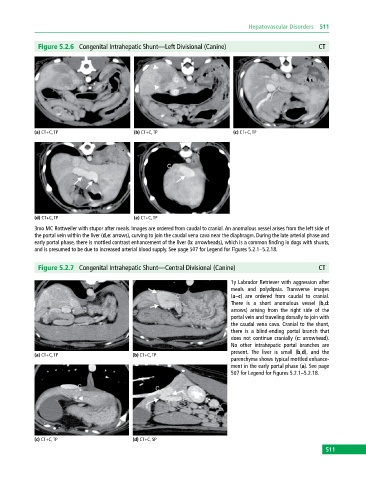

Figure 5.2.6 Congenital Intrahepatic Shunt—Left Divisional (Canine) CT

(a) CT+C, TP (b) CT+C, TP (c) CT+C, TP

(d) CT+C, TP (e) CT+C, TP

3mo MC Rottweiler with stupor after meals. Images are ordered from caudal to cranial. An anomalous vessel arises from the left side of

the portal vein within the liver (d,e: arrows), curving to join the caudal vena cava near the diaphragm. During the late arterial phase and

early portal phase, there is mottled contrast enhancement of the liver (b: arrowheads), which is a common finding in dogs with shunts,

and is presumed to be due to increased arterial blood supply. See page 507 for Legend for Figures 5.2.1–5.2.18.

Figure 5.2.7 Congenital Intrahepatic Shunt—Central Divisional (Canine) CT

1y Labrador Retriever with aggression after

meals and polydipsia. Transverse images

(a–c) are ordered from caudal to cranial.

There is a short anomalous vessel (b,d:

arrows) arising from the right side of the

portal vein and traveling dorsally to join with

the caudal vena cava. Cranial to the shunt,

there is a blind‐ending portal branch that

does not continue cranially (c: arrowhead).

No other intrahepatic portal branches are

present. The liver is small (b,d), and the

parenchyma shows typical mottled enhance-

ment in the early portal phase (a). See page

507 for Legend for Figures 5.2.1–5.2.18.